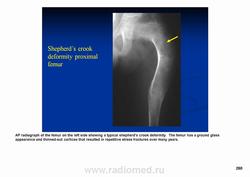

Фиброзная дисплазия — заболевание, характеризующееся нарушением развития (дисплазия) скелета, при котором нормальная кость замещается фиброзной тканью с элементами диспластически изменённой кости. Выделяют монооссальную (около 85% случаев), мономелическую (поражено несколько соседних костей одной конечности, плечевого или тазового пояса) и полиоссальную (около 5% случаев) формы. Фиброзная дисплазия как аномалия развития иногда сочетается с внескелетными расстройствами: 1) полиоссальная форма поражения сочетается с преждевременным половым созреванием и пигментными пятнами на коже в виде кофейных пятен (Albright’s syndrome); 2) сочетание фиброзной дисплазии с миксомами мягких тканей (Mazabraud’s syndrome). Встречается в любом возрасте, наиболее часто в первые 3 десятилетия жизни (70% больных). Монооссальная форма несколько чаще встречается у лиц мужского пола, при полиоссальной форме соотношение лиц мужского и женского пола 2 : 1. Поражается любая кость, наиболее частая локализация: проксимальная часть бедренной кости, большеберцовая и плечевая кости, рёбра, кости черепа, шейного отдела позвоночника. Поражение костей позвоночника только в 2,5% случаев.